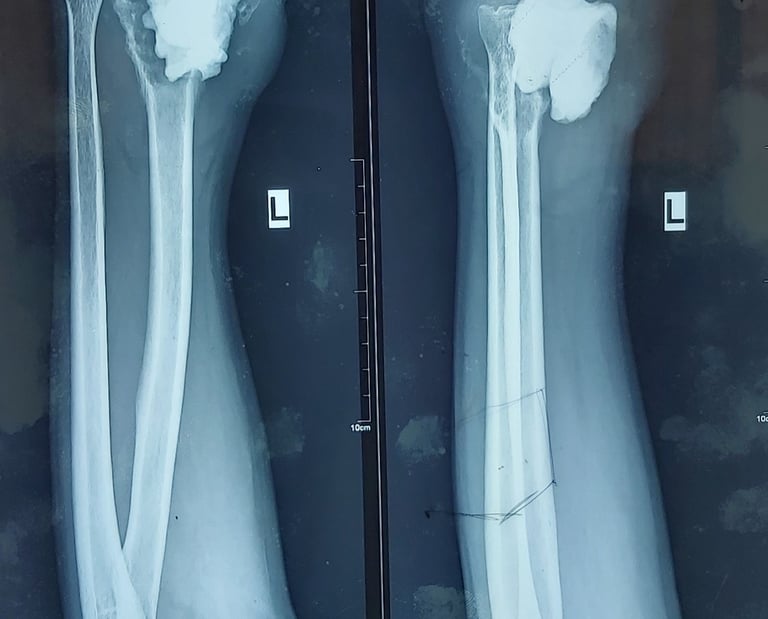

Management of Paediatric Proximal Tibia Osteosarcoma - A Novel Technique of Preservation of Physeal Growth

Osteosarcoma is a malignant tumor, the treatment of which is controversial between amputation and limb salvage surgery. Osteosarcoma occurring in a child is a challenge to manage due to the arrest of limb and the resultant limb length discrepancy. The management options for a child less than eight years of age are very limited.